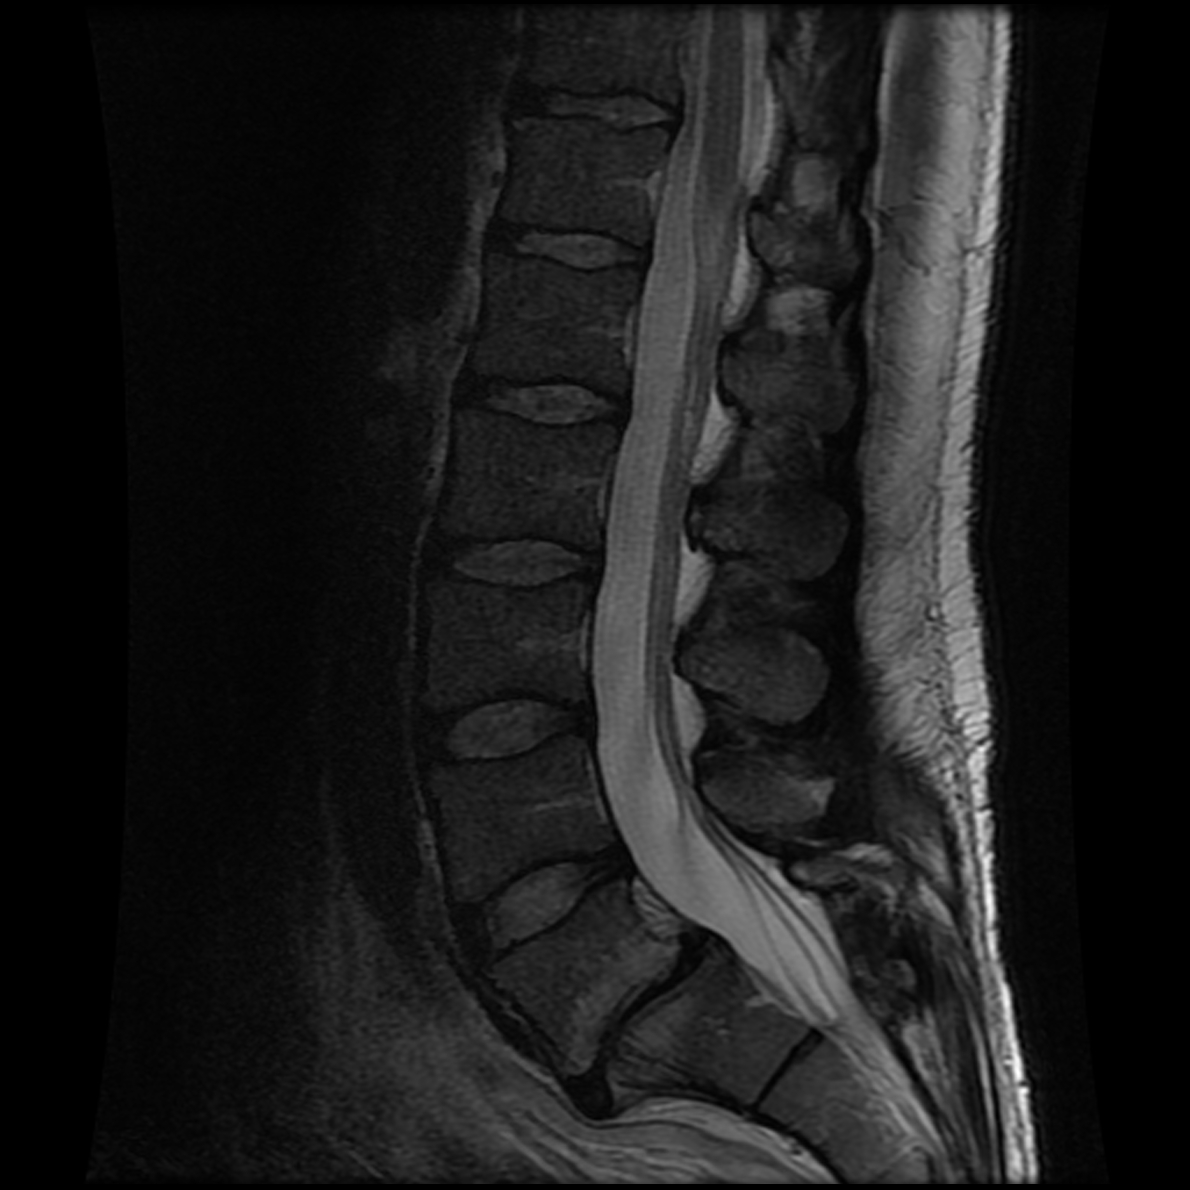

June 2020 MRI

IMPRESSION

- Healed femoral-sided ACL tear with partial attenuation of the proximal ACL fibers.

- Progressive healing of horizontal oblique tear of the medial meniscus posterior horn.

- Chronic inferiorly displaced meniscal flap tear at the lateral meniscus posterior

horn-root junction, less conspicuous than on prior MR imaging. Resolution of previously

noted horizontal longitudinal tear of the body-posterior horn segments. - No new evidence of internal derangement. No acute osseous abnormality.